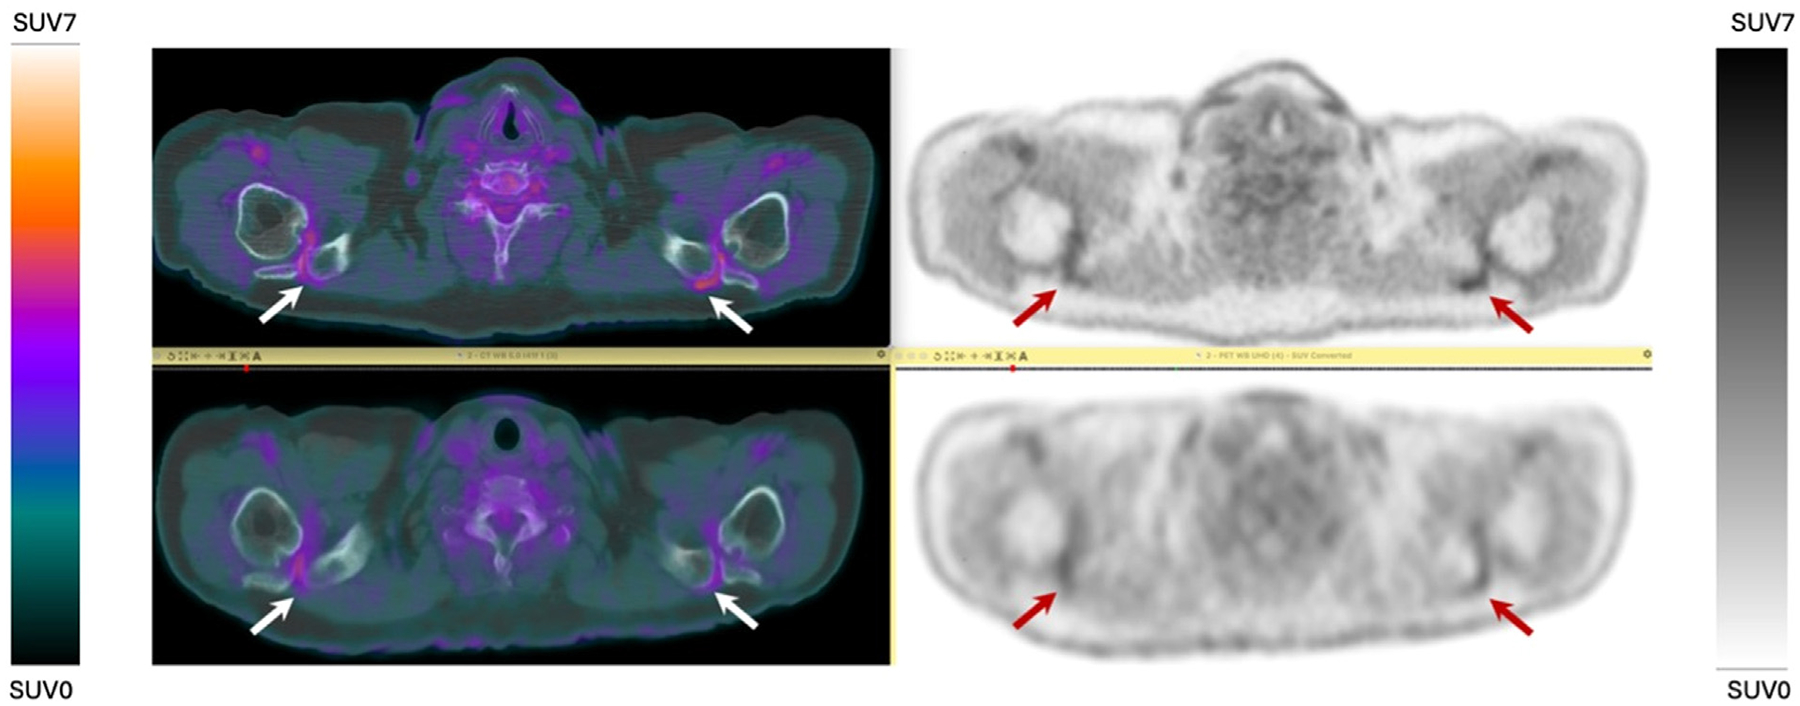

Inflammatory disorders historically have been difficult to monitor with conventional PET imaging due to limitations including radiation exposure, lack of validated imaging biomarkers, low spatial resolution, and long acquisition durations. However, the recent development of long-axial field-of-view (LAFOV) PET/CT scanners may allow utilization of novel noninvasive biomarkers to diagnose, predict outcomes, and monitor therapeutic response of inflammatory conditions. LAFOV PET scanners can image most of the human body (if not the entire body) simultaneously in one bed position, with improved signal collection efficiency compared to conventional PET scanners. This allows for imaging with shorter acquisition durations, decreased injected radiotracer dose, prolonged uptake times, or a combination of any of these. In addition, LAFOV PET scanners enable whole-body dynamic imaging. Altogether, these intrinsically superior capabilities in assessing both local and systemic diseases, have allowed these scanners to make increasingly significant contributions to the assessment of inflammatory conditions. This review aims to further explore the role and benefits of LAFOV scanners for imaging various inflammatory conditions while addressing future developments and challenges faced by this technology.